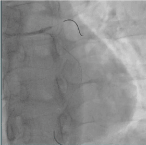

Trans-radial coronary angiogram revealed tortuous and aneurysmal dilatation (ectatic vessels) of all three major coronary arteries (Figure 3a, 3b) with huge thrombus in the proximal segment of left circumflex (LCx) artery, the culprit lesion was identified. Left coronary system was engaged with XB 3.0 6-French guiding catheter through right radial access with 6F sheath. The lesion was crossed by Run through NS floppy (Terumo) hydrophilic 0.014 inches wire. Among different strategies to deal with huge thrombus burden such as Plain Old Balloon Angioplasty (POBA), thrombus aspiration and intracoronary glycoprotein IIb/IIIa inhibitor, we proceeded with thrombus aspiration. Thrombuster II (Kaneka Corporation) thrombus aspiration catheter introduced into the target vessel and suctioning performed. Blood clots aspirated as shown (Figure 4). After few aspirations, failed to do further suctioning and planned to flush as the catheter may get blocked from aspirated thrombus. Some degree of resistance was felt while removing the catheter from the vessel. The thrombus aspiration catheter finally came out with slight pulling force but noted that the tip was missing (Figure 5). Angiographically, the tip of Thrombuster II catheter seen attached to the guidewire (Figure 6). The guidewire can move freely along the mid and distal LCx but failed to withdrawal at the proximal LCx area.

Figure 3a. Left coronary artery Figure 3b. Right coronary artery